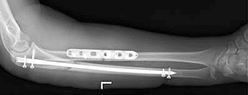

Переломы костей предплечья

Предплечье формирует 2 кости: локтевая и лучевая. Предплечье имеет сложную анатомию. В этой области расположился большой спектр анатомических образований (сухожилий, мышц, нервов), способствующих нормальному функционированию всей верхней конечности и кисти. Наиболее часто встречающиеся травмы в области предплечья:

- переломы дистального метаэпифиза лучевой кости;

- переломы лучевой кости в «типичном месте»;

- диафизарные переломы.

Основным методом выбора лечения таких пациентов является внутренний остеосинтез пластинами. При переломах обеих костей предплечья принято выполнять остеосинтез двумя накостными пластинами, что позволяет снизить травмирование мягких тканей. Операцию проводят через два отдельных доступа.